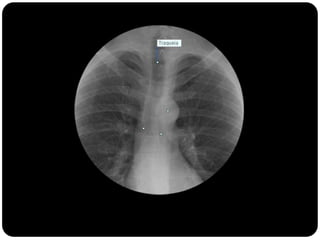

Repare como a traquéia apresenta-se em um

exame em expiração...